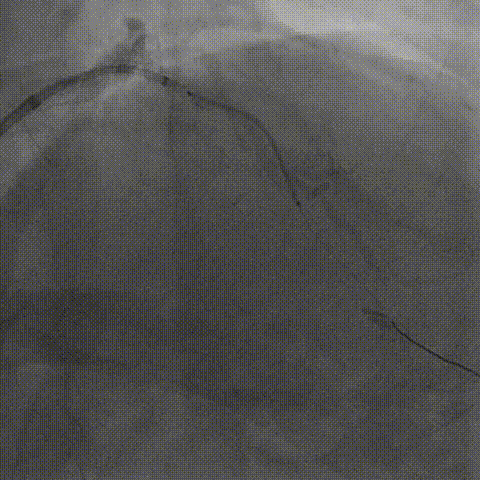

左冠造影

将EBU 3.0指引导管坐窦底,Sion导丝飘入

AO刹车导丝,2.5球囊预扩张

LAD近段-LM IVUS提示为270°环形钙化

LAD近段-LM 选择shockwave4.0*12mm,间断触发脉冲,每5个脉冲为一组,只4atm治疗,防止患者缺血省略6atm扩张,每次回撤Guiding,使用5个周期;

复查LAD近段-LM IVUS,钙化环明显断裂